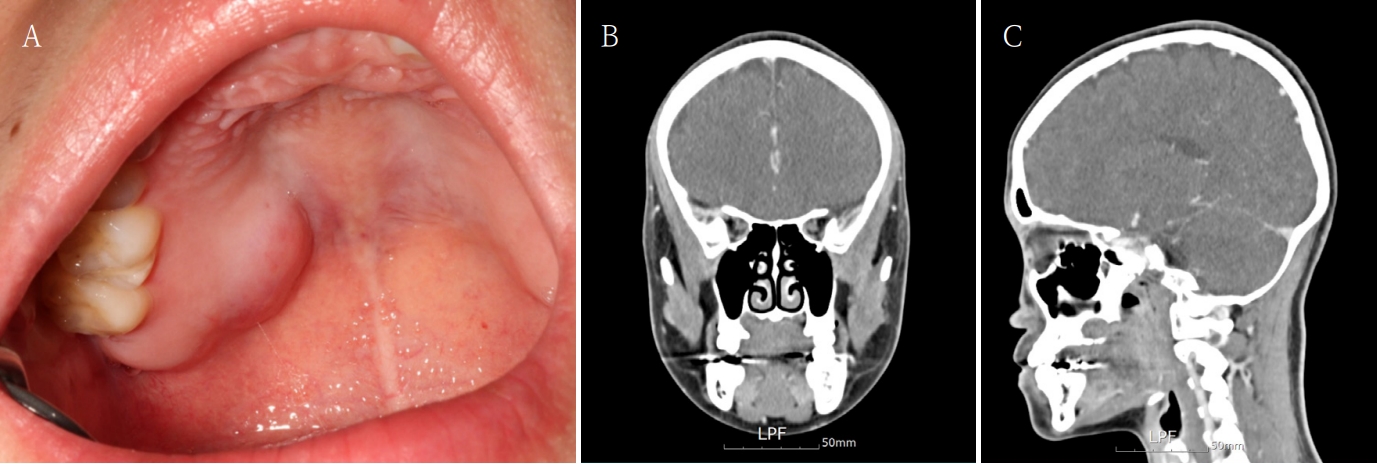

A 26-year-old female patient was referred to our clinic for definitive diagnosis and treatment due to bulging lesion on the right posterior palatal region. The patient reported being aware of the lesion for approximately one month. Notable swelling was observed in the right posterior hard palate. Upon palpation, a firm swelling exhibiting slight elasticity was noted, without any evidence of fluctuation. The lesion did not extend beyond the palatal midline and measured approximately 2.5 cm x 2 cm x 2 cm. There was no color change on the overlying mucosa and the surface of the lesion was smooth without ulcers (Fig. 1A). It revealed no pain, and aspiration yielded no content. Adjacent teeth showed no clinical features such as pain or discomfort, and the palate involving the lesion exhibited no sensory abnormalities.

A. A round, protruding lesion is observed in the posterior region of the right hard palate, with no associated symptoms such as pain. B and C. Facial CT images show no significant changes in size or bone destruction compared to the previous examination.

A facial CT was performed, which revealed a 16 mm x 12 mm x 12 mm radiolucent cystic lesion with central faint high-density content (Figs. 1B and C). Incision biopsy was also done. Histopathological results confirmed the diagnosis of pleomorphic adenoma. Considering the possibility of recurrence, it was decided to exercise both the lesion and the overlying mucosa under general anesthesia. For the surgical defect that may arise postoperatively, a buccal fat pad free graft was designated as the reconstructive method. Under general anesthesia, a mass excision in the right palate with a buccal fat pad free graft was performed. The lesion with overlying mucosa was excised using an electrocautery device. The size of the excised lesion was approximately 2.5 cm x 2 cm x 2 cm. The border of the lesion was clear without adhesion. bony erosion of the palatal region was observed at the lesion site, with no evidence of maxillary sinus perforation. The posterior area of the right maxillary second molar was incised, and the dissection was performed to expose the buccal fat pad. A portion of the exposed fat pad was harvested and grafted into an excised defect as a free graft. The grafted buccal fat pad was sutured to the surrounding mucosa (Fig. 2). A prefabricated palatal shell was placed to protect the surgical field. Histopathological result of the excised lesion confirmed pleomorphic adenoma, with tumor-free resection margins. During the hospitalization period, the grafted buccal fat pad remained stable without evidence of complications.